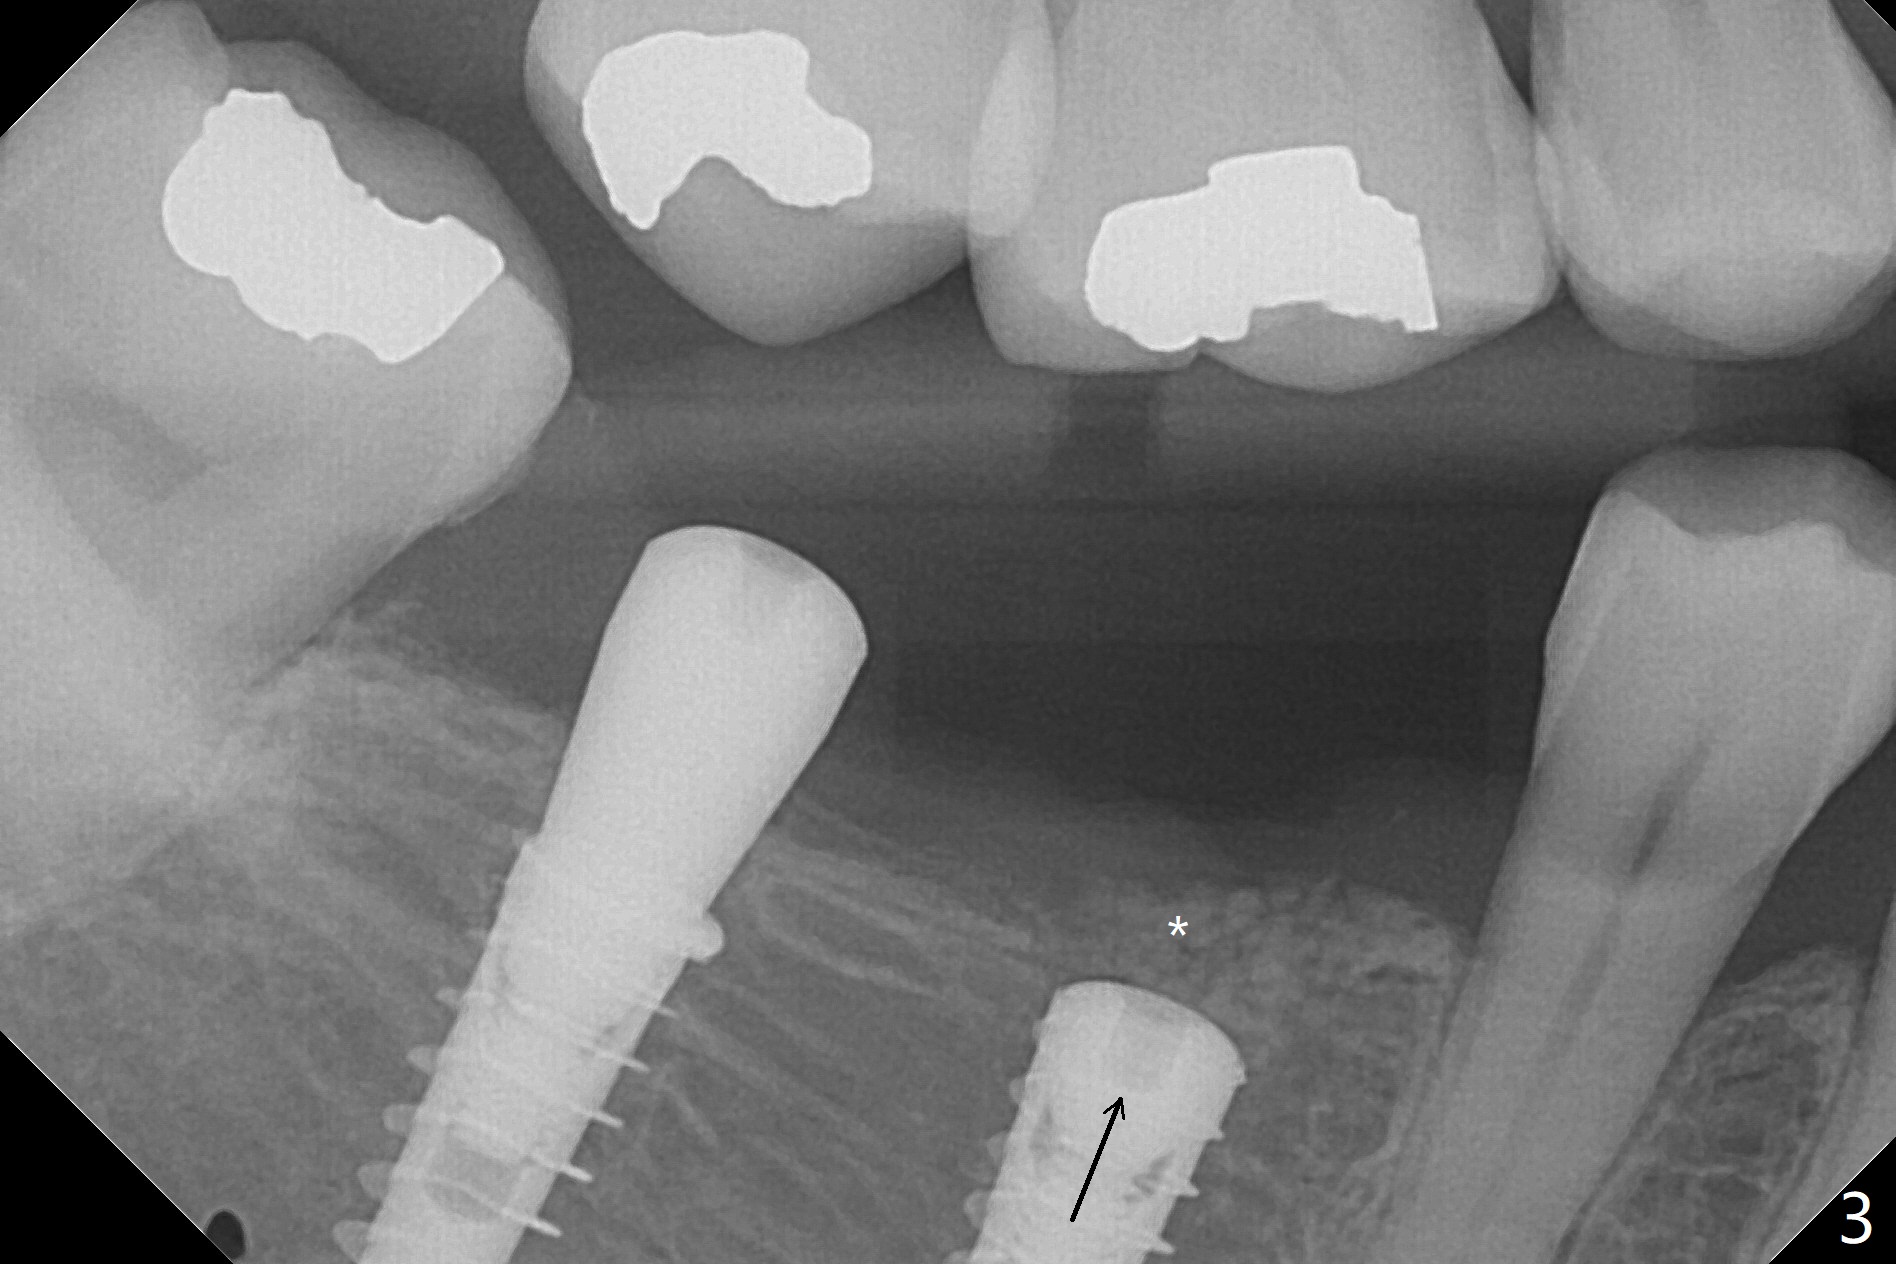

害怕病人局麻药很慢起效,术中身体会动,术中决定减小右下6,7植体直径0.5毫米(与导板设计相比),一旦植体越过牙槽嵴顶骨皮质,稳定性突然减低(图一)。尽管扭力10-15Ncm,为了避免二期手术,放置愈合基台(图二),6基台没有就位(箭头),因为植体种太深了,牙槽骨阻挡(*)基台就位。当取出6基台时,植体一起旋出,重新植入时,就没有种那么深(图三:箭头,与图一,二对比)。由于扭力低,只好放置愈合帽,骨粉(*),GEM Cap(6-9月胶原膜)和牙周胶水。由于导板设计缘故,左上5拔除,种植后,才开始左上3一段式植体植入(图四),5也植入太深(图五),必须放置最小直径最长袖(cuff)的基台(图六),今后导板即刻植牙先不要到达设计深度。术后一周CT显示尖牙植体位于牙槽骨内(图七 (>:腭侧牙槽嵴))。Bone graft fills in the buccal apical defect at #13 one week postop (Fig.8 <). 术后两个月左上3临时牙冠折裂,5松动(图九,十),后者取出衬里,软组织愈合。术后8个月左上3,5取模,右下6 uncover,愈合帽表面覆盖骨质,把7号牙愈合基台放到6号牙上,而7号牙放置4.5x4(4)毫米修复基台,固定牙周敷料,这样6号牙伤口不必缝合。术后8.5个月右下6放置4.5x7.5(4)毫米基台,发现7基台没有就位(图十一:箭头),通过旋转7 基台,终于就位(图十二),螺丝往下移位(与图十一:横线对比),但是基台边缘太低,不利于取模。改用5.5x4(5)毫米UF基台,临床上不能就位,局麻使用5.5毫米Profile Drill后,才能就位(图十三),螺丝下端超越最低螺沟(横线)。